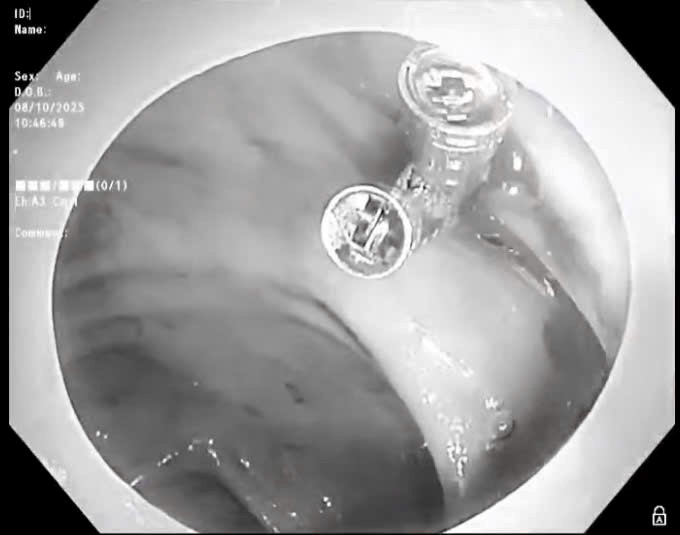

Lần đầu tiên tại Việt Nam bảo hiểm y tế chi trả tối đa phẫu thuật kích thích não sâu cho bệnh nhân Parkinson

Thứ Tư, ngày 07/01/2026 03:03Đây là trường hợp Parkinson đầu tiên tại Việt Nam được bảo hiểm y tế chi trả tối đa cho phẫu thuật kích thích não sâu. Việc bệnh nhân đầu tiên được hưởng quyền lợi này là dấu mốc quan trọng,...